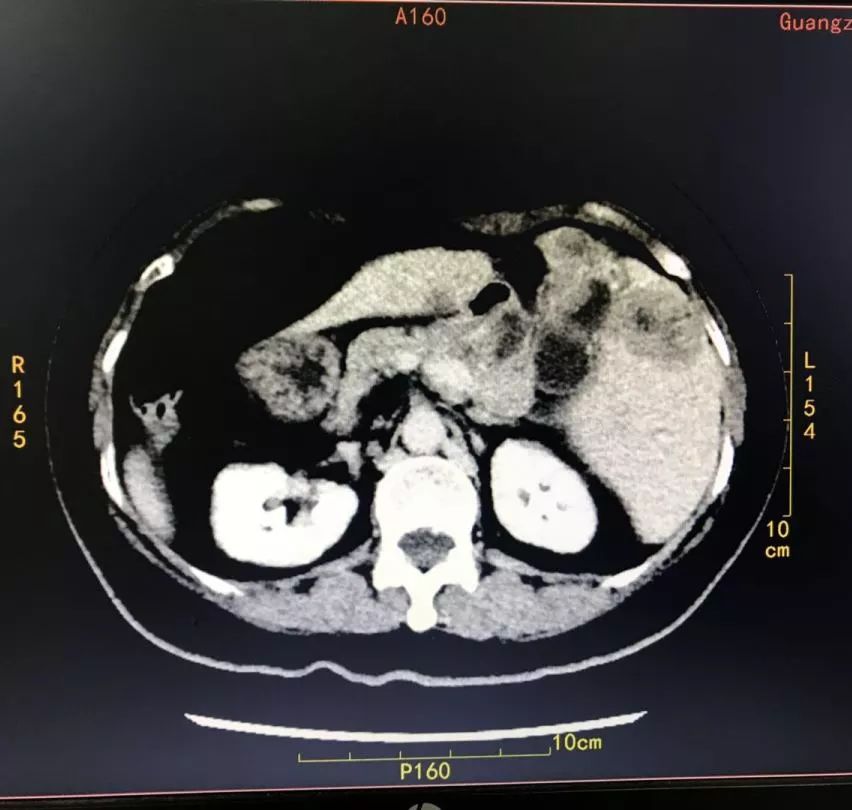

CT提示:全内脏反位

CT提示:胆囊癌伴肝内多发转移